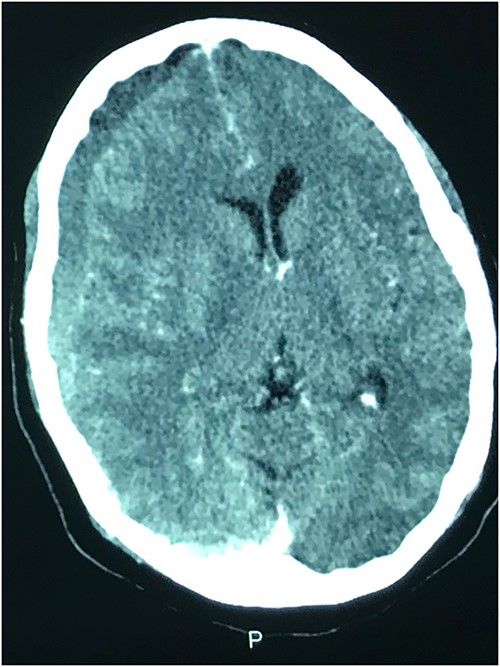

Prior to this, he had been managed for low back pain and lumbar spondylosis. Spine MRI done prior to neurosurgery consultation did not explain the lower extremity motor weakness. Brain CT done revealed bilateral fronto-parietal CSDH (Fig. 2A). He was worked up for urgent surgical evacuation through a bilateral frontal and parietal burr hole drainage. He made good neurologic improvement and his lower extremity power returned to normal on the 8th day post op. Post-operative CT scan done at 4 weeks follow-up showed satisfactory resolution of the haematoma (Fig. 2B).

(A) Pre-op showing bilateral CSDH. (B) Post op complete resolution of CSDH.